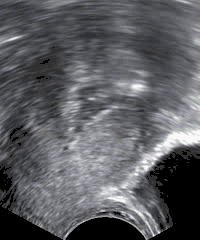

Postmenopausal bleeding

In postmenopausal bleeding, guidelines from the United States consider transvaginal ultrasonography to be an appropriate first-line procedure to identify which women are at higher risk of endometrial cancer. A cut-off threshold of 3 mm or less of endometrial thickness should be used for in women with postmenopausal bleeding in the following cases:

- Not having used hormone replacement therapy for a year or more

- Usage of continuous hormone replacement therapy consisting of both an estrogen and a progestogen

A cut-off threshold of 5 mm or less should be used for women on sequential hormone replacement therapy consisting both of an estrogen and a progestogen.

It the endometrial thickness equals the cut-off threshold or is thinner, and the ultrasonography is otherwise reassuring, no further action need be taken. Further investigations should be carried out if symptoms recur.

If the ultrasonography is not reassuring, hysteroscopy and endometrial biopsy should be performed. The biopsy may be obtained either by curettage at the same time as inpatient or outpatient hysteroscopy, or by using an endometrium sampling device such as a pipelle which can practically be done directly after the ultrasonography.